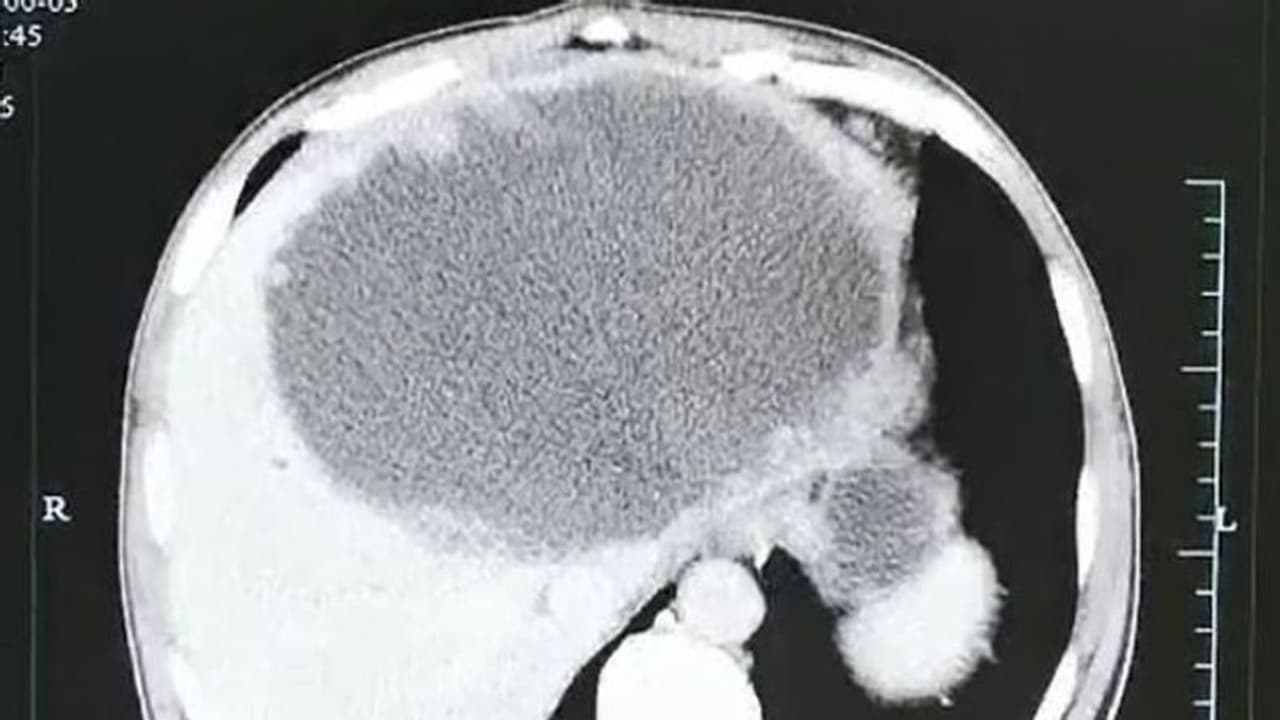

കടുത്ത വയറുവേദന മൂലം ആശുപത്രിയിലെത്തിയ അമ്പത്തിയഞ്ചുകാരന്റെ എക്സ് റേ ഫലം കണ്ട ഡോക്ടര്മാര് പോലും ഞെട്ടിത്തരിച്ചുപോയി. കരളിന്റെ വലത്തേ ഭാഗത്ത് മുഴുവനായി പഴുപ്പ് നിറഞ്ഞത് പോലെ തീരെ ചെറിയ മുഴകള് കൊണ്ട് നിറഞ്ഞിരിക്കുന്നു. ഇത് എന്ത് പറ്റിയതാണെന്ന് മാത്രം ആദ്യം ഡോക്ടര്മാര്ക്ക് മനസിലായില്ല.

ഇതിന്റെ മാംസത്തില് നിന്നും ചെറിയ വിരകള് (പാരസൈറ്റ്) അദ്ദേഹത്തിന്റെ ശരീരത്തില് കയറിപ്പറ്റി. ശേഷം കരളിന്റെ വലത്തേ അറയിലായി വിരകള് താമസവും തുടങ്ങി. മാസങ്ങള് കൊണ്ട് ഇവ അവിടെ മുട്ടയിട്ട് പെറ്റ് പെരുകി. പഴുപ്പ് നിറഞ്ഞത് പോലെ എക്സ് റേയില് കണ്ട തീരെ സൂക്ഷ്മമായ മുഴകളെല്ലാം തന്നെ ഈ മുട്ടകളായിരുന്നത്രേ.